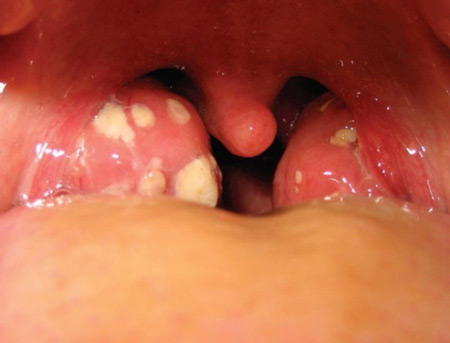

При обследовании у взрослого небных миндалин при гнойном тонзиллите на их поверхности можно заметить желтоватый налет гноя и пробки — светлые пятна, немного выступающие над воспаленной поверхностью.

- Фолликулярная форма заболевания сопровождается отечностью лимфоузлов и образованием явно выраженных гнойных образований.

- Лакунарная форма характеризуется наличием желтого или белого налета в лакунах, а гнойнички появляются позже.

Гнойная ангина проявляется выделением гнойной жидкости из воспаленных миндалин. Гной представляет собой продукт жизнедеятельности возбудителей заболевания (стрептококки, стафилококки), которые обитают в углублениях миндалин.

Лакуны — это естественные углубления на поверхности миндалин. Они являются местом размножения бактерий во время бактериального ангины, что приводит к образованию гнойных отложений.